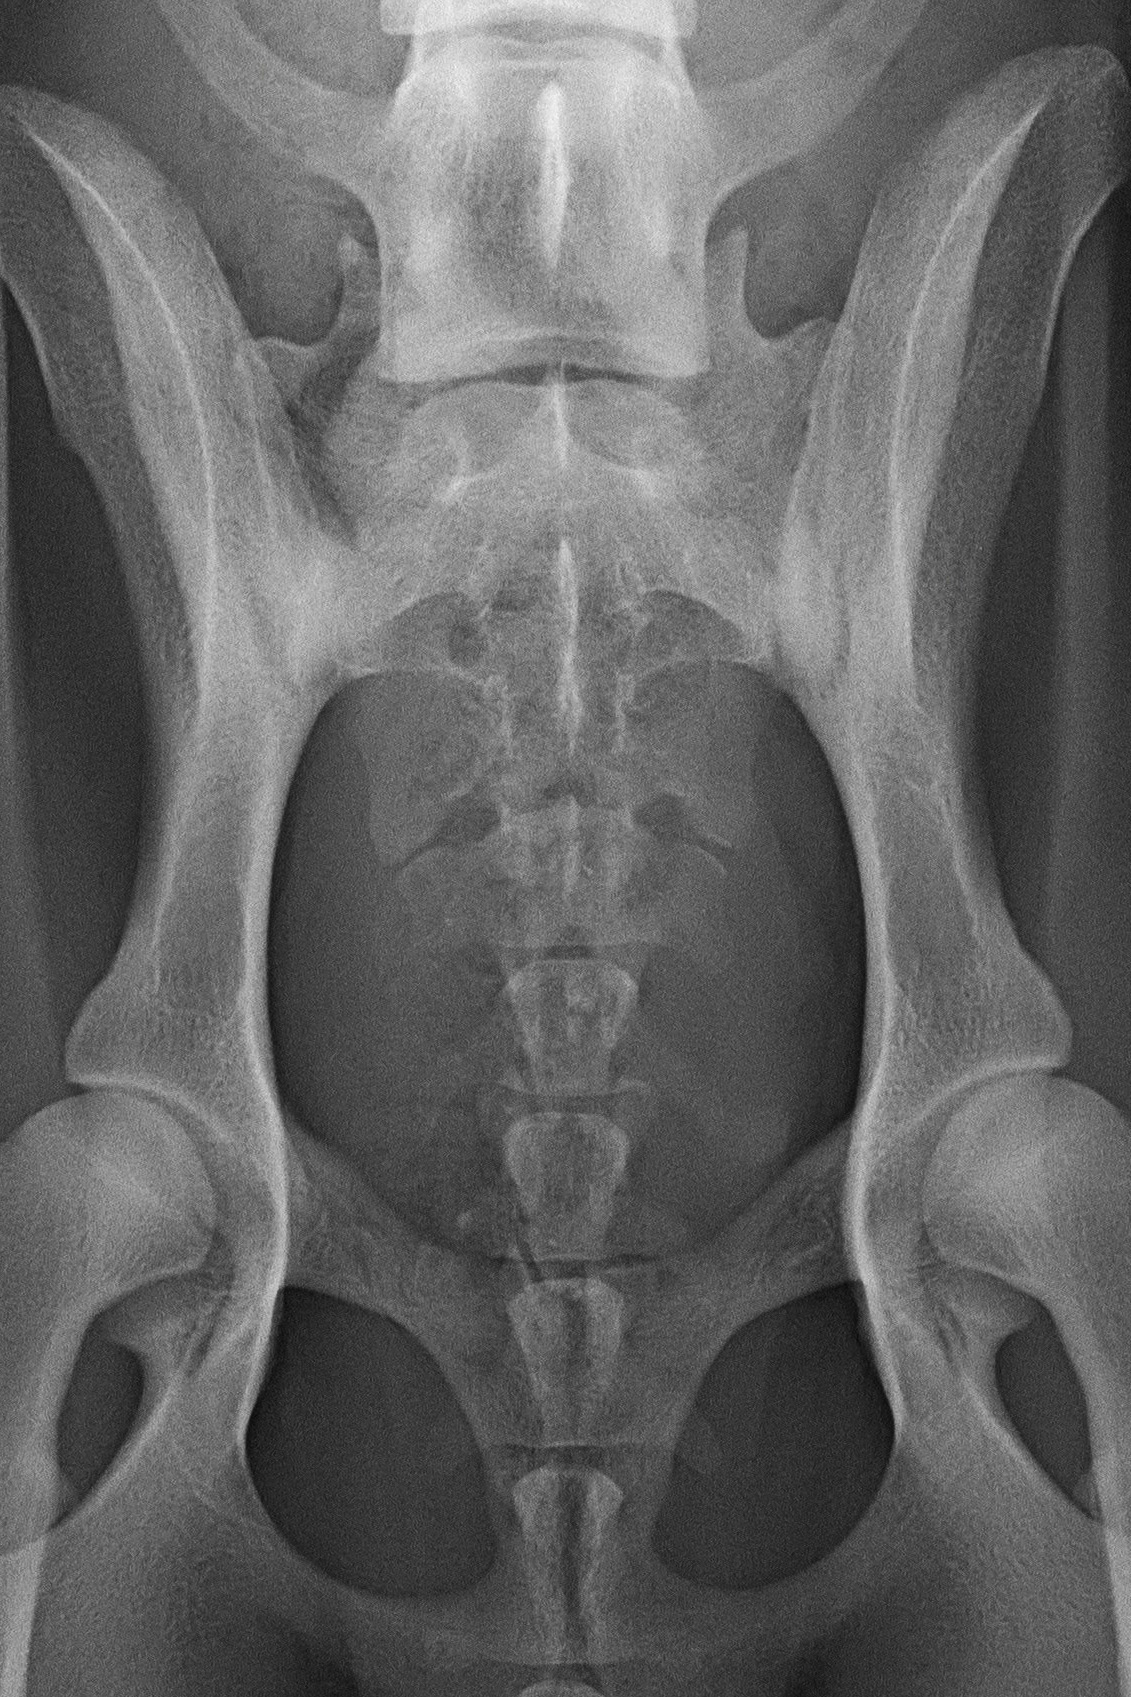

(3) 7 měsíců VD 1

(3) typ 3 po korekci polohy pánve

(4) 7 měsíců VD 2

(4) typ 3 po korekci polohy pánve 2